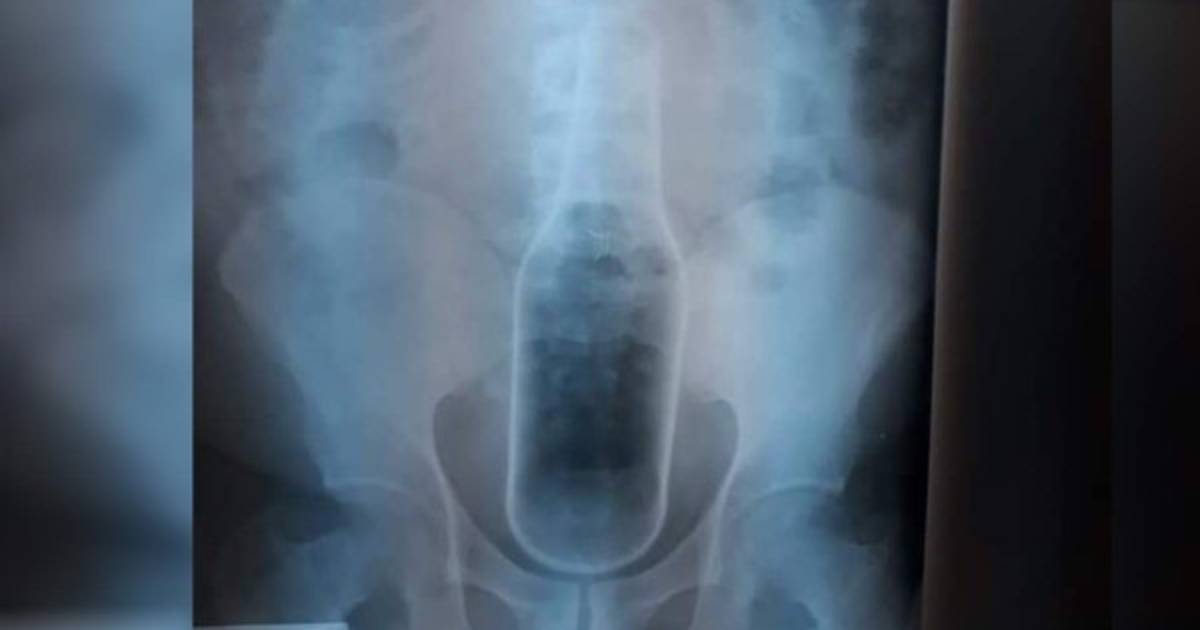

Un equipo de médicos le extrajeron la botella tras practicarle una cirugía.

Un hondureño fue operado de emergencias en el Hospital Regional del Sur en Choluteca luego que se metiera una botella de cerveza en el ano.

Médicos especialistas le extrajeron la botella tras practicarle una cirugía y ahora se encuentra interno mientas se recupera establemente.

'El paciente padece de problemas de hemorroides y estaba haciendo la introdución de esta botella, se la introdujo toda y no pudo sacarla', explicó un doctor del hospital público donde fue atendido.

'Tuvo que hacerse intervención quirúrgica, una laparotomía para extraer el cuerpo extraño', indicó.